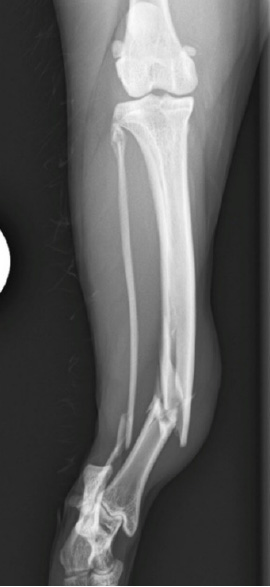

膝関節のレントゲン撮影を行います。

目で確認することのできない関節の内部の様子を評価します。

|

左のレントゲン画像は脛骨の前方への変位、関節液の増加が認められています。 |